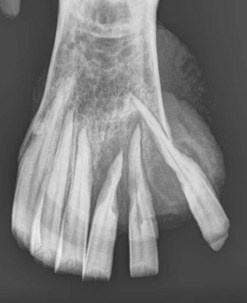

Fig. 13.35 Oligodontia. The pony in (A) has anodontia of 308, 408 and 108, although the deciduous remnant (‘cap’) of one lower 08 is still present.

image

The pony in (B) has only 5 teeth in both mandibular rows, with large overgrowths of the upper 10s and 11s and secondary diastemata formation between the upper 09s and 10s.